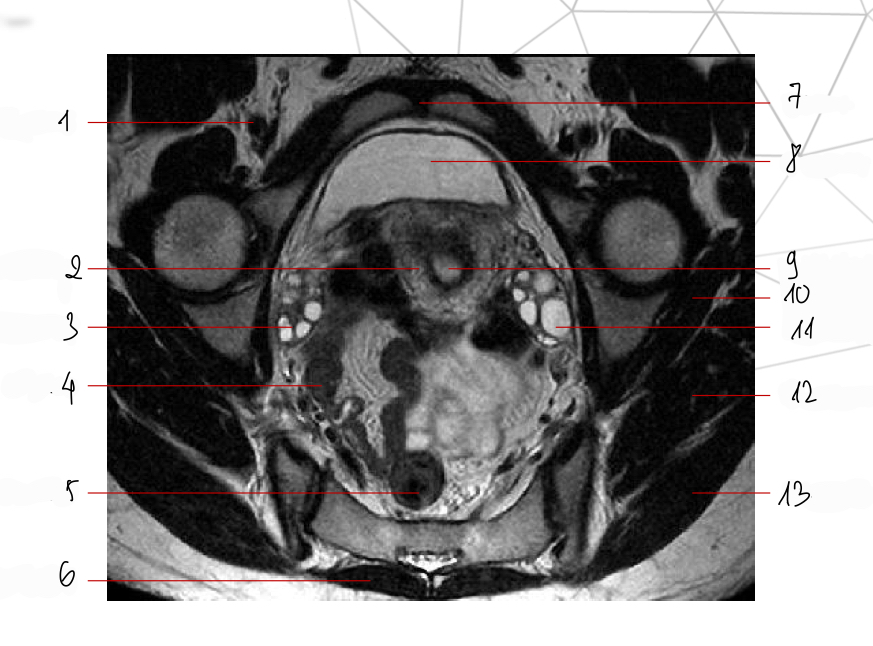

Mốc gp, chuỗi xung, thì

Thì nghỉ, T2w ax

chuỗi xung, thì, mốc gp

T2 cor, thì nghỉ